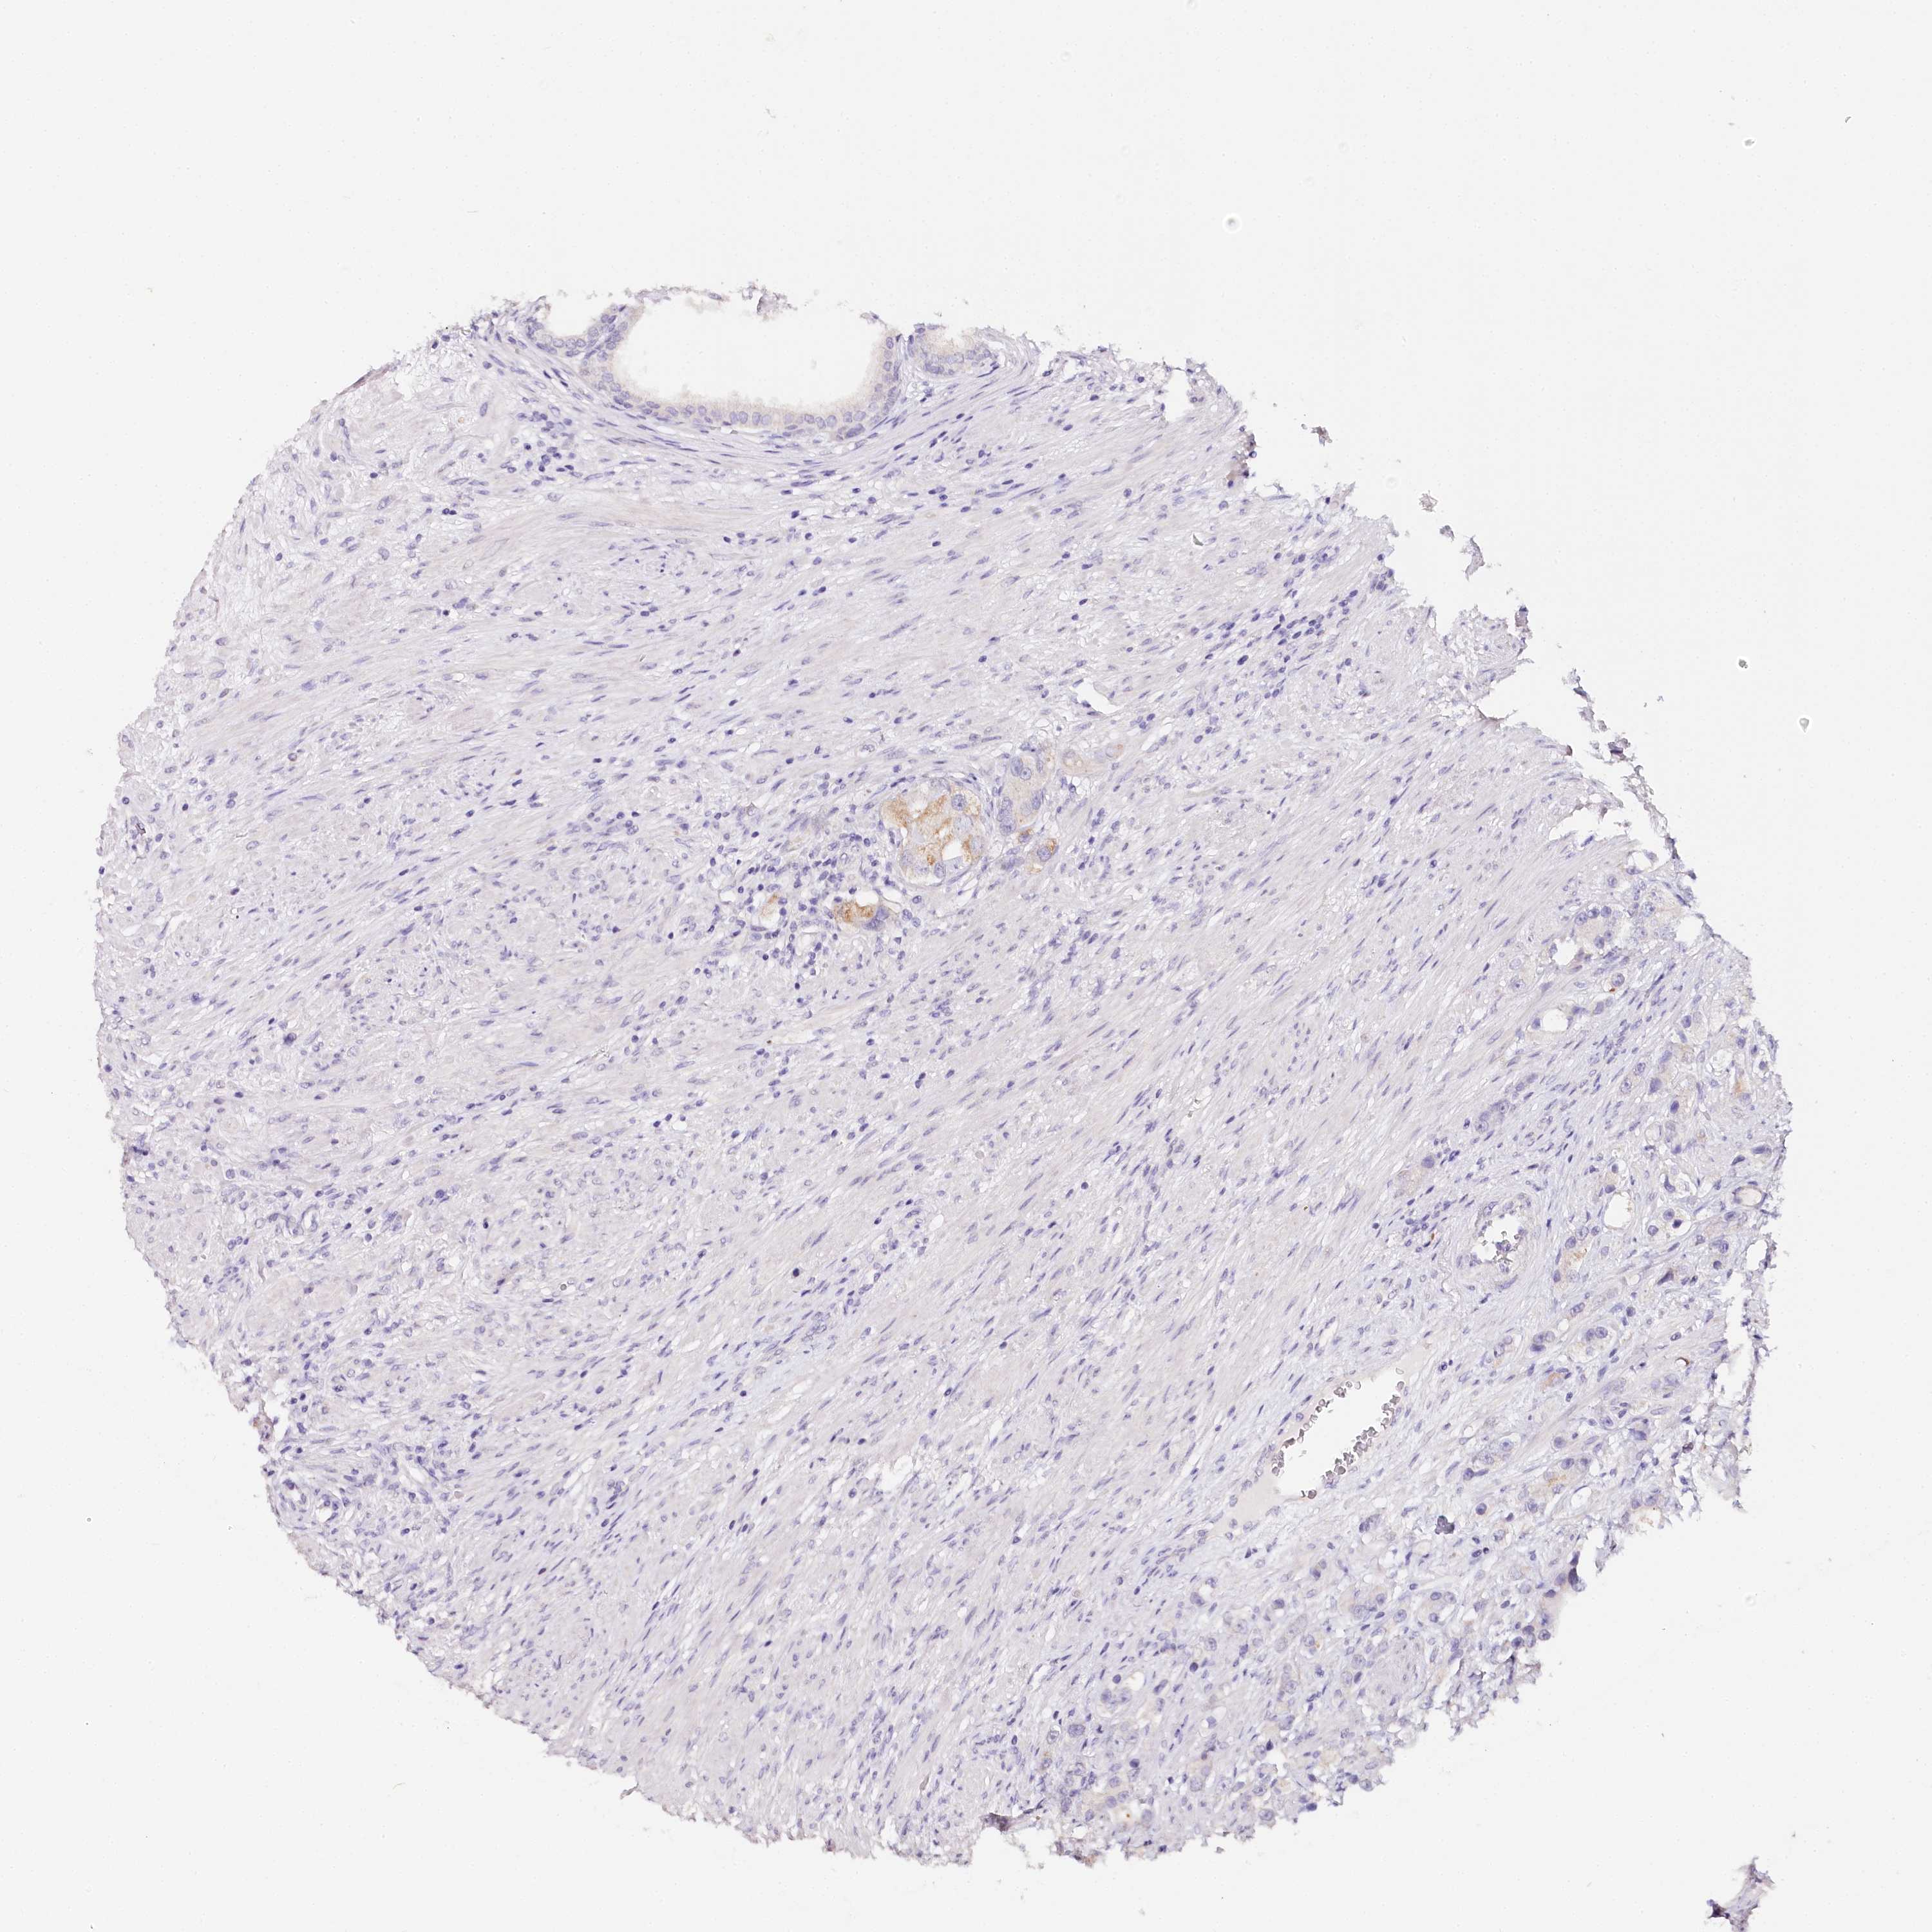

PROSTATE CANCER - Protein expressioni

A mouse-over function shows sample information and annotation data. Click on an image to view it in a full screen mode. Samples can be filtered based on level of antibody staining by selecting one or several of the following categories: high, medium, low and not detected. The assay and annotation is described here.

Note that samples used for immunohistochemistry by the Human Protein Atlas do not correspond to samples in the TCGA dataset.

Antibody stainingi

Antibody staining in the annotated cell types in the current human tissue is reported as not detected, low, medium, or high, based on conventional immunohistochemistry profiling in selected tissues. This score is based on the combination of the staining intensity and fraction of stained cells.

Each image is clickable and will lead to virtual microscopy that enables deeper exploration of all samples and also displays staining intensity scores, fraction scores and subcellular localization as well as patient and tissue information for each sample.

Antibody CAB002973

Antibody CAB039238

Antibody CAB039239

Antibody CAB072876

Staining

High

Medium

Low

Not detected

Intensity

Strong

Moderate

Weak

Negative

Quantity

>75%

75%-25%

<25%

None

Location

Nuclear

Cytoplasmic/membranous

Cytoplasmic/membranous,nuclear

Adenocarcinoma, Low grade

Adenocarcinoma, Medium grade

Adenocarcinoma, High grade

Adenocarcinoma, NOS